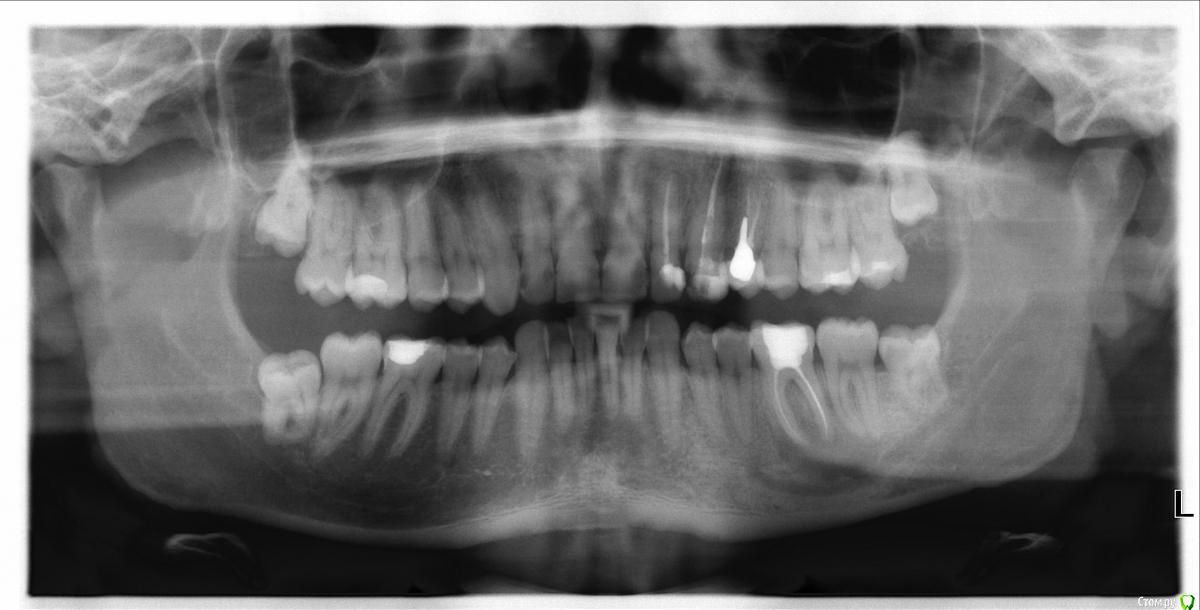

alexkirs Опубликовано 12 ноября, 2016 Поделиться Опубликовано 12 ноября, 2016 Добрый день. У меня на 6 снизу нашли крупную кисту. Врач сказал, что можно полечить, но вероятность, что лечение поможет процентов 10 не больше. Лечение получается достаточно дорогое, вот и думаю стоит ли тратить деньги на неясный результат или проще сразу удалить зуб. Помогите сделать выбор, пожалуйста. Панорамный снимок в приложении. Ссылка на КТ https://yadi.sk/d/BAV8sEZHyUwxmСпасибо Ссылка на комментарий

DmitrySH Опубликовано 12 ноября, 2016 Поделиться Опубликовано 12 ноября, 2016 Все верно написала.Отвлекусь от "кисты" на ОПТГ, что с 11,21? артефакты? Ссылка на комментарий

St. Опубликовано 12 ноября, 2016 Поделиться Опубликовано 12 ноября, 2016 11, 21 по кт без особенностей. Так что артефакты скорее всего. В 23( левый клык) есть тоже воспаление на корне. Нужно планово перелечиавать. Ссылка на комментарий

DmitrySH Опубликовано 12 ноября, 2016 Поделиться Опубликовано 12 ноября, 2016 (изменено) По оптг и 22 тоже требует ревизии Изменено 12 ноября, 2016 пользователем DmitrySH Ссылка на комментарий